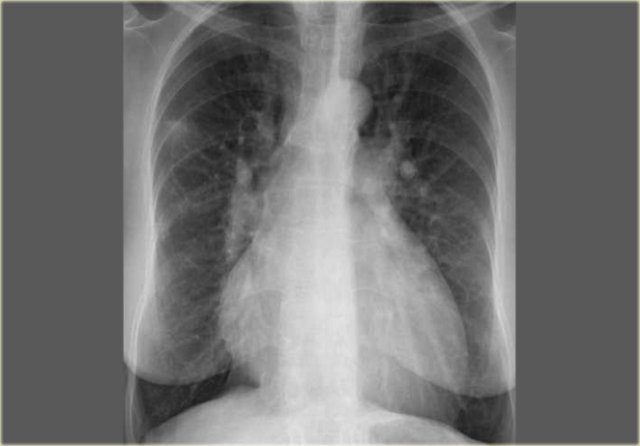

On the left a chest film of a 6-month old boy with stridor and cough.

The trachea is deviated to the left, otherwise the chest film is normal.

So there is some mass effect on the right side.

On the left the reconstructions demonstrating a double aortic arch.

There are branches coming off the right arch and branches coming off the left arch.